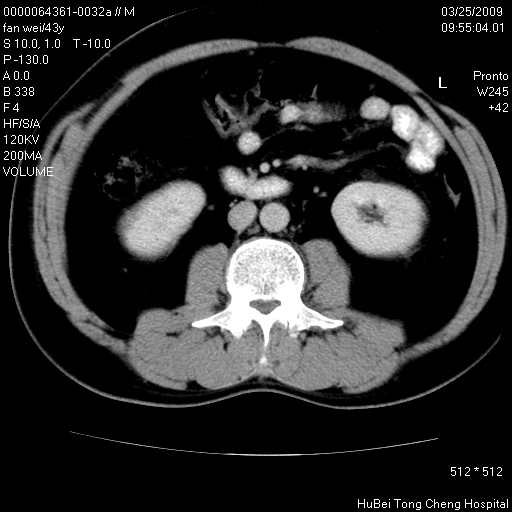

双肾ct轴位平扫+增强扫描(层厚10mm,螺距1.0,重建间隔10mm),图像如下:

多囊肾的影像诊断标准:有阳性家族史,年龄<30岁,单侧或双侧肾脏有两个肾囊肿;30~59岁,两侧肾脏各有两个肾囊肿;60岁以上,每侧肾脏有4个囊肿。敏感性和特异性达86%和80%。

双肾多发性囊肿

左肾体积变大,支持多囊肾。

双侧多囊肾!

囊肿数得清,肾功能正常,考虑多发肾囊肿.另外,右肾后极突向肾周间隙的那个病灶是不是错构瘤,请楼主调窗看看.